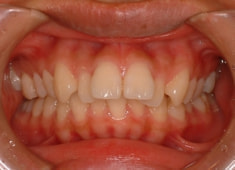

治療前